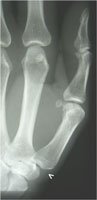

Auf dem Röntgenbild sehen Sie einen verschmälerten Gelenkspalt, der in fortgeschrittenen Fällen komplett verschwunden ist. Handchirurgen sprechen hier auch von einer Knochenglatze, da das Gelenk keine Knorpelschicht mehr aufweist. Das Endstadium der Rhizarthrose besteht in der Gelenksteife.